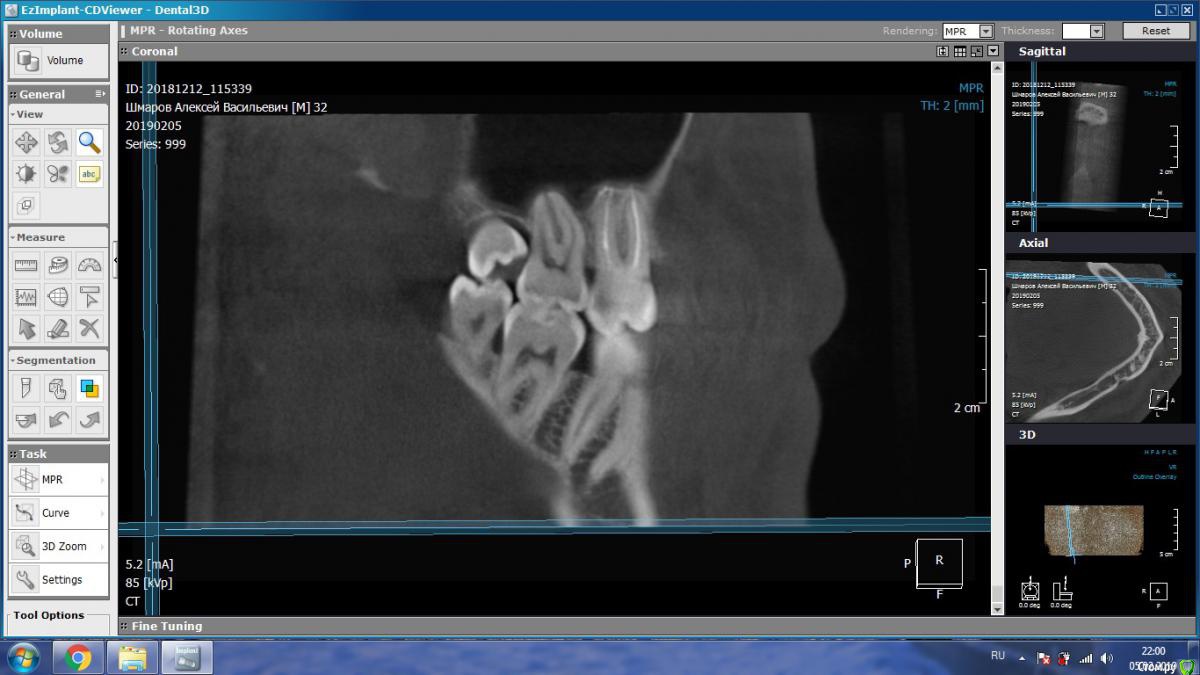

aleks.k Опубликовано 6 февраля, 2019 Автор Поделиться Опубликовано 6 февраля, 2019 Срезы Ссылка на комментарий

aleks.k Опубликовано 6 февраля, 2019 Автор Поделиться Опубликовано 6 февраля, 2019 Еще один срез, может быть более удачный чем первые в этой проекции Ссылка на комментарий

DmitrySH Опубликовано 6 февраля, 2019 Поделиться Опубликовано 6 февраля, 2019 Срезы Очень хорошо. Теперь как первые три, но увеличить 16 зуб. Остальные нам мало интересны, пазуха тоже Ссылка на комментарий

DmitrySH Опубликовано 7 февраля, 2019 Поделиться Опубликовано 7 февраля, 2019 В шестом зубе похоже еще 1 канал есть Ссылка на комментарий

DmitrySH Опубликовано 7 февраля, 2019 Поделиться Опубликовано 7 февраля, 2019 Я так понимаю что меня записали на удаление, по причине того, что стоматолог не обладает квалификацией для такого лечения? Ведь нужен именно эндодантист. Допустим что канал есть. Если его лечить, по цене примерно сколько это стоит? В Калуге думаю нет таких специалистов. Хотя бы примерно. И в случае лечения есть ли гарантия на такой зуб? Еще нужен микроскоп. Потому как если бы канал был хорошо виден, то его бы сразу нашли и обработали. Ссылка на комментарий